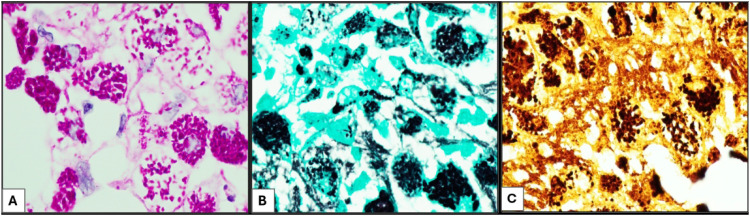

Whipple disease is a rare systemic disease caused by Tropheryma whipplei. It can present with a wide range of nonspecific symptoms that might overlap with underlying medical conditions, posing a diagnostic challenge. We present a 61-year-old man with a past medical history of rheumatoid arthritis and chronic inflammatory demyelinating polyneuropathy, who presented with persistent leukocytosis and supraclavicular lymphadenopathy. A positron emission tomography scan revealed hypermetabolic activity in the supraclavicular, abdominal, and pelvic lymph nodes along with a myocardial hypermetabolic lesion, concerning a lymphoproliferative disorder versus sarcoidosis. A supraclavicular lymph node excisional biopsy revealed complete architectural effacement by a diffuse foamy histiocytic infiltrate without granuloma formation or necrosis. The differential diagnosis included underlying infection, histiocytic neoplasm, lymphoproliferative disorder, storage disorder, and others. Immunostains show the histiocytic cells were positive for CD68 and CD163, while negative for S100, CD1a, kappa, lambda, and BRAF V600E. Grocott-Gömöri's methenamine silver and periodic acid-Schiff (PAS) stains demonstrated diffuse intracytoplasmic granular staining that was resistant to diastase treatment. Gram, acid fast bacilli, and Fite stains were negative. Electron microscopy revealed rod-shaped organisms with a trilaminar plasma membrane, morphologically consistent with T whipplei. Polymerase chain reaction was positive for T whipplei, confirming the diagnosis. Although rare, Whipple disease should be considered in immunocompromised patients presenting with nonspecific nongastrointestinal symptoms and lymphadenopathy clinically simulating lymphoma. Periodic acid-Schiff D-positive inclusions, along with confirmatory molecular results, are crucial for diagnosis. Whipple disease is a curable disease that can be lethal if unrecognized, emphasizing the importance of heightened awareness for early diagnosis and timely treatment.